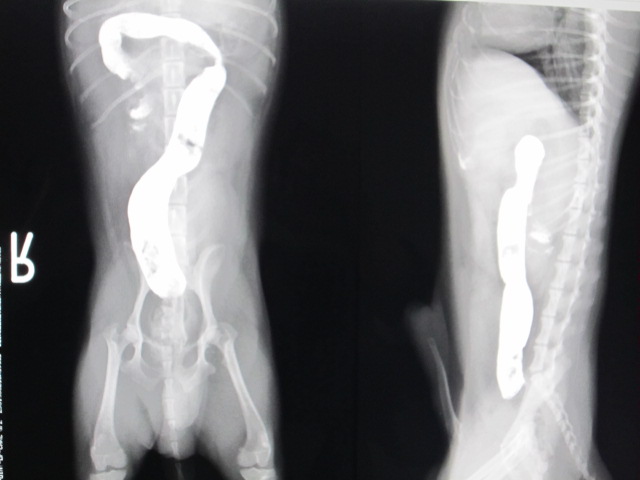

術前

術前のレントゲンです。

バリウム投与24時間後も結腸までバリウムが流れませんでした。

術後

術後のレントゲンです。

バリウムは結腸まで流れました。